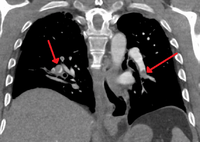

Segmental and subsegmental pulmonary emboli on both sides

CT pulmonary angiography showing a "saddle embolus" at the bifurcation of the main pulmonary artery and thrombus burden in the lobar arteries on both sides.